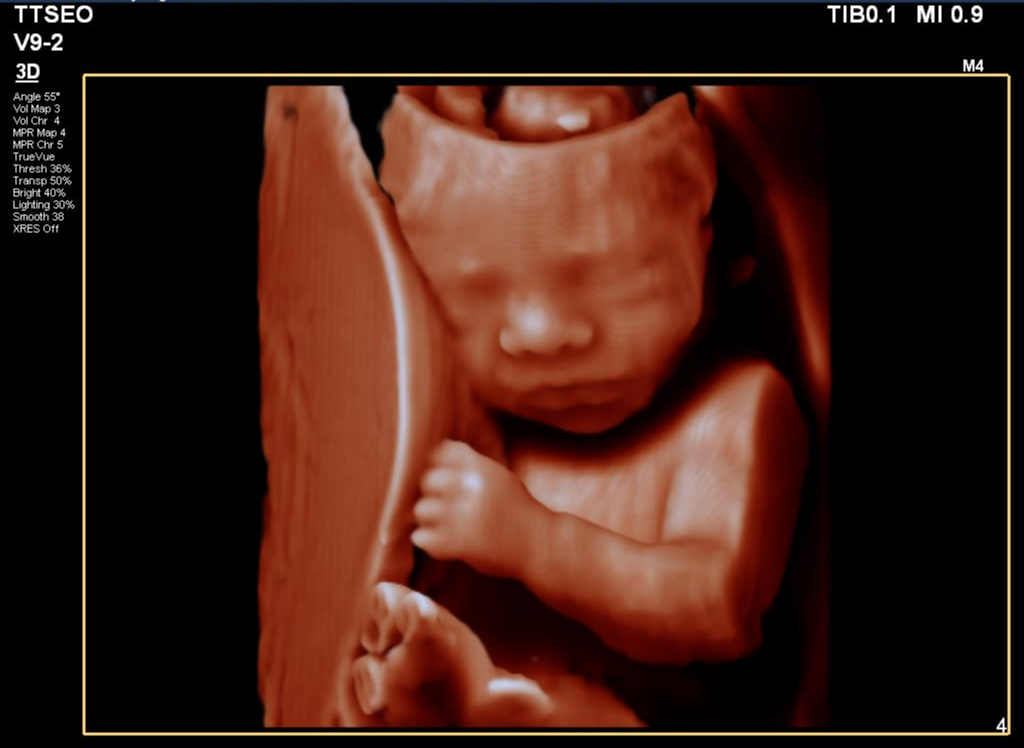

3D Ultrasound from 26 Weeks

A fun ultrasound to see your baby’s face in 3D or even 4D if the baby is in the right position. You might even see your baby sucking its thumb or playing with its toes! You’ll receive all the images (including videos) on a USB stick, along with printed pictures. The cost for this scan is €75, and it lasts 30 minutes. You can schedule as many 3D ultrasounds as you like!

3D Ultrasound